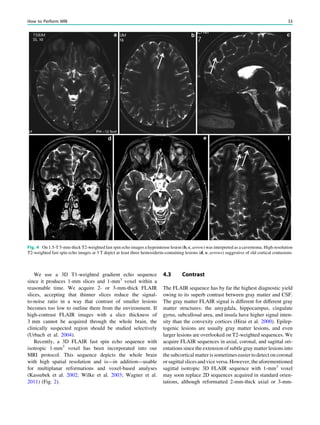

4.3 Contrast.................................................................................. 33

4.4 Contrast Medium Injection ................................................... 34

5 MRI Interpretation.............................................................. 34

6 MRI Protocols...................................................................... 34

References...................................................................................... 35

Abstract